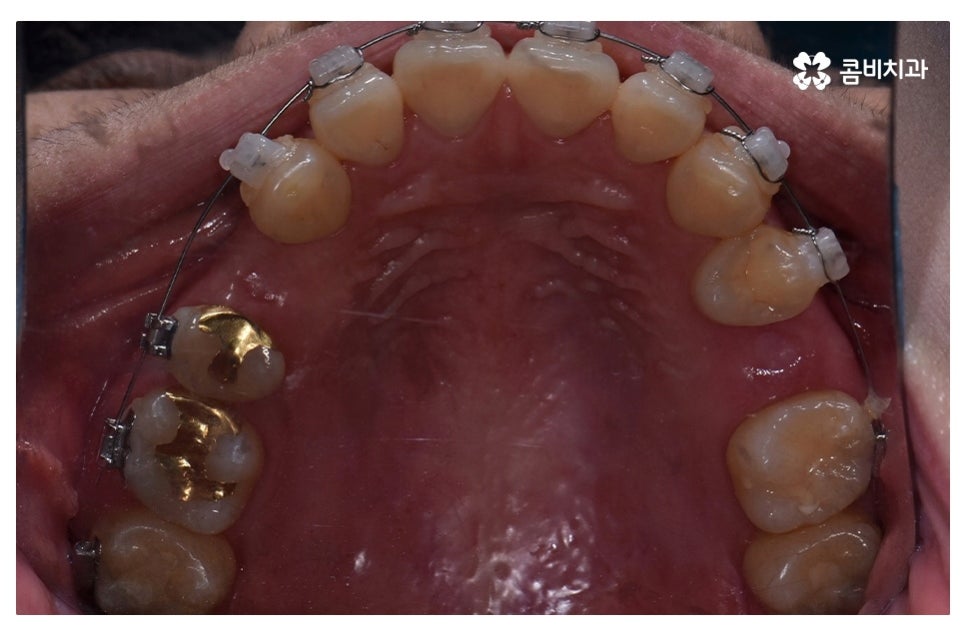

이번 포스팅에서 보인 덧니교정 사례의 경우 기능이 적은 작은 어금니를

발치하여 교정이 진행되었으며 발치를 진행하는 경우

작은 어금니를 발치하는데 충치 등으로 인해 손상이 큰 치아를

발치하는 경우가 일반적이라고 할 수 있어요.

요즘은 교정 장치의 선택에 있어서 다양한 선택이 가능하지만

보편적으로는 본 포스팅의 사례처럼 클리피씨 교정이 많이 선호되고 있어요.